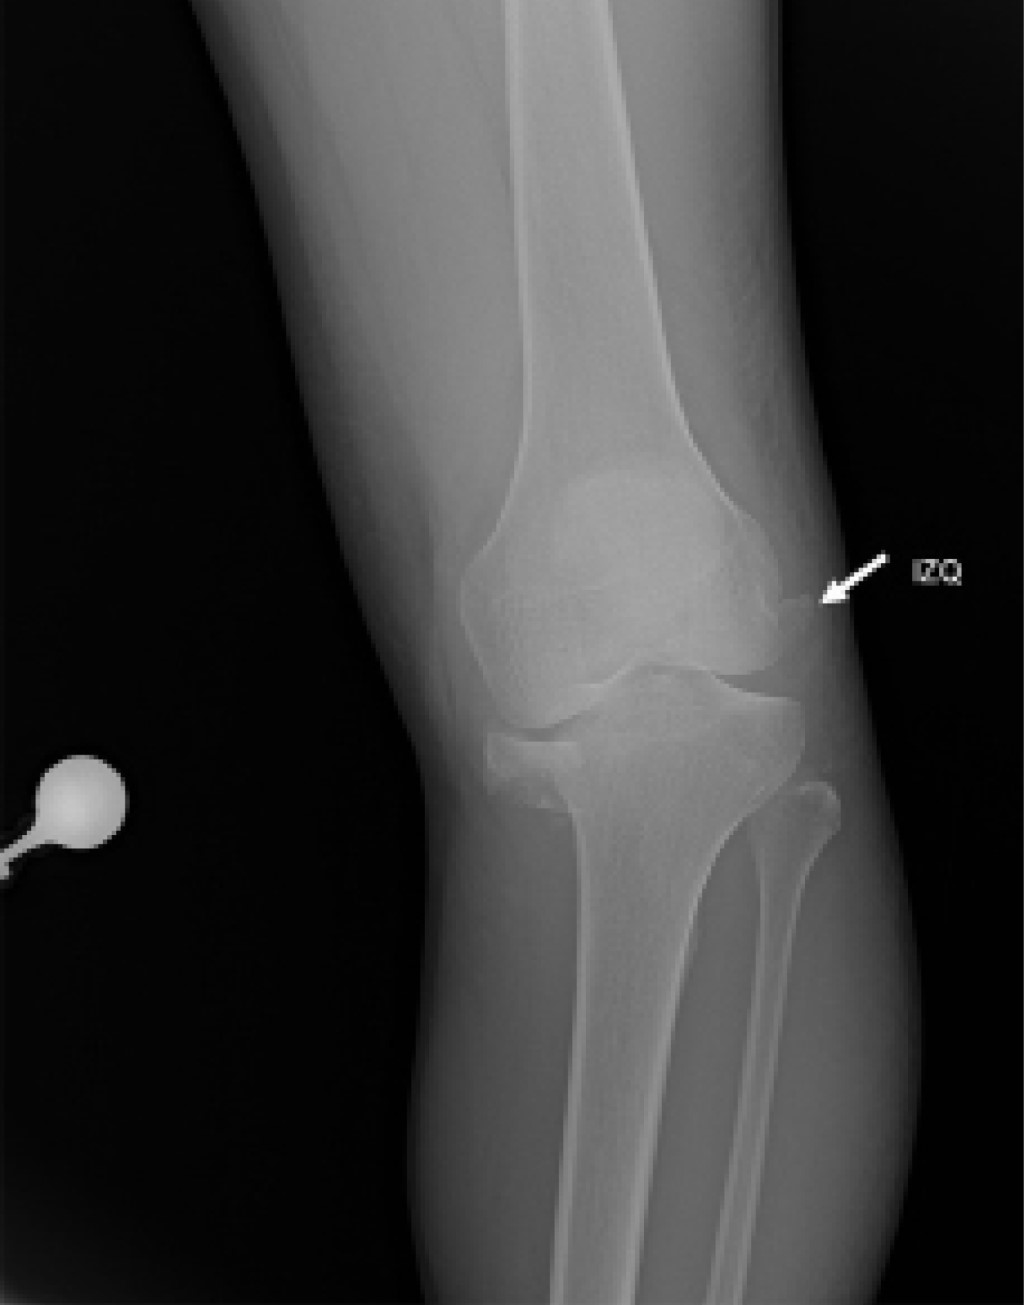

El segundo escenario es mucho más complejo de abordar, se presenta cuando el paciente ingresa al servicio de urgencias con la rodilla reducida, haciendo del diagnóstico de la luxación de rodilla un reto para el clínico, en el cual las radiografías iniciales tienen un papel valioso en la evidencia de hallazgos característicos que pueden sugerir el diagnóstico de luxación como la apertura de los espacios articulares tibiofemorales (Figura 4), fracturas del cóndilo femoral, fracturas de espinas tibiales anterior y posterior, signo del ligamento arcuato (Figura 5) o el signo de Segond (Figura 6).3

El "signo del arcuato" corresponde a una avulsión en la cabeza del peroné, sitio donde se inserta el complejo arcuato (ligamento arcuato, ligamento poplíteo fibular, tendón conjunto del bíceps y ligamento colateral fibular), sugestivo de lesión de la esquina posterolateral de la rodilla; hay que tener en cuenta que hasta 89% de pacientes con lesiones de esquina posterolateral presentan lesión de ligamento cruzado anterior o posterior y que debe considerarse en contexto de sospecha de luxación de rodilla.42,43